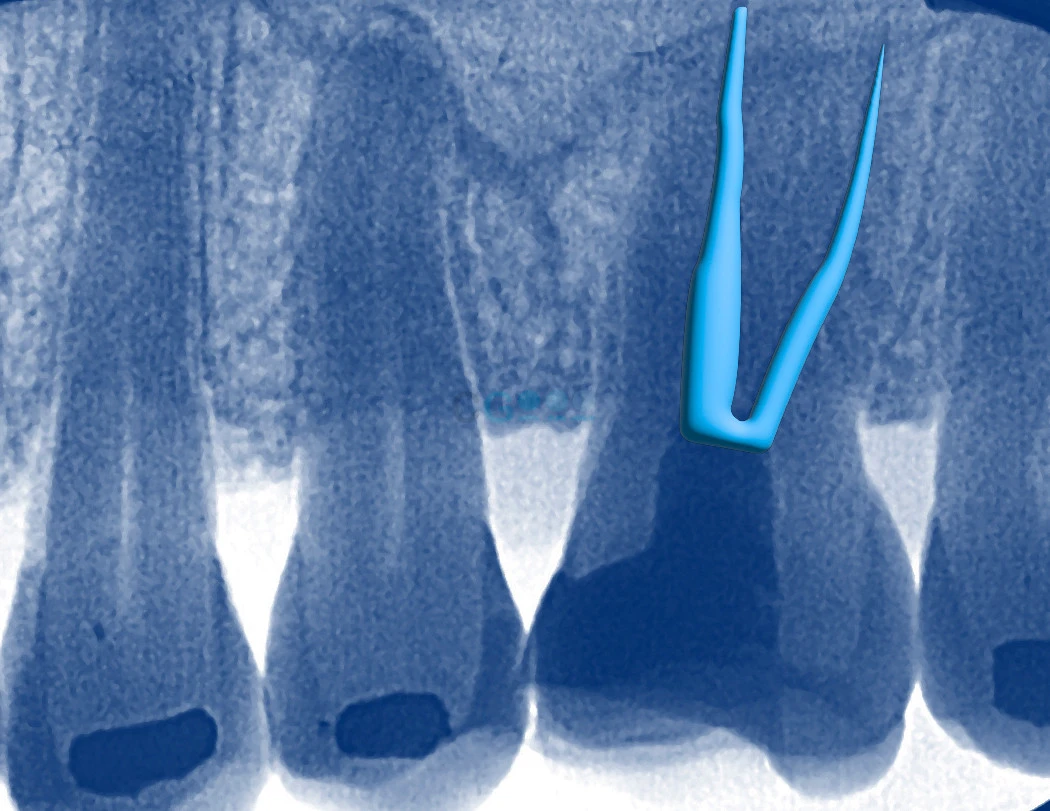

Endodoncia

La endodoncia, conocida comúnmente como "tratamiento de conductos", se realiza cuando el nervio de un diente está dañado o infectado. Consiste en limpiar el interior del diente, eliminar el tejido afectado y sellarlo para evitar futuras infecciones y dolor. Con la endodoncia evitamos la extracción de los dientes.